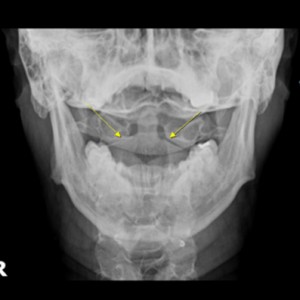

안면 두개골 엑스레이 검사

Submento Vertex View 포함

안면 두개골 CT

경추 1,2번의 변위 파악